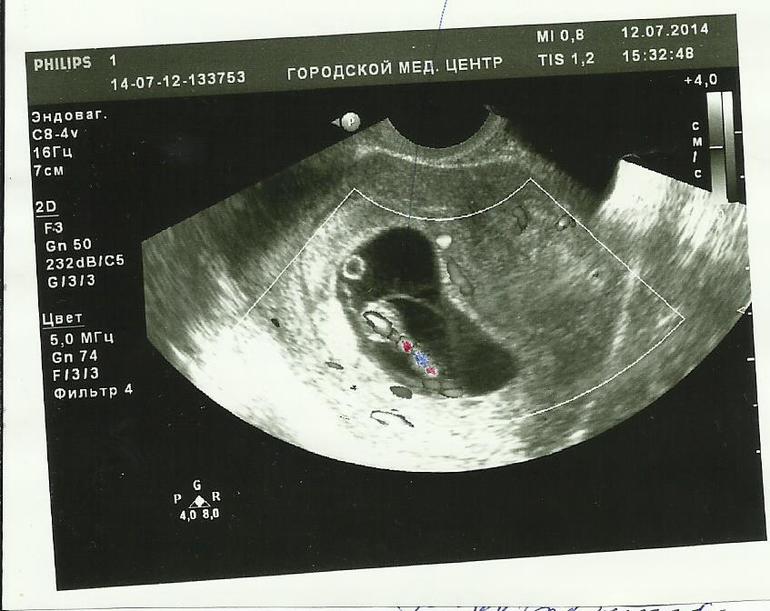

На этом снимке врач отметил " чрезмерно толстую пуповину "С казала , что ребенку очень тяжело дышать, ему не хватает кислорода! И опять сделала акцент на том , что пузыря второго не должно быть вообще! То , что он есть ,это очень плохо! Мне лучше прервать беременность т.к ребенок может родится с разными отклонениями сердечной и дыхательной системами! А пить антибиотики на этом сроке опасно тем , что ребенок так же может родиться с отклонениями......

С.А провел мне целую лекцию на эту тему зачитав и указав на якобы неведомый пузырь(со слов первого врача) и жидкости внутри него и пуповина у нас хорошая ,и кислорода хватает! Я показала ему первое узи и он тактично промолчал но при том по фактам своего исследования полностью опроверг его !